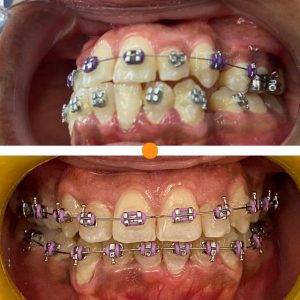

Tratamientos Ortodoncia Blanqueamiento dental Zoom Contacto 72 2795 9597 Marcar Ahora Envia whatsapp Visita nuestro facebook